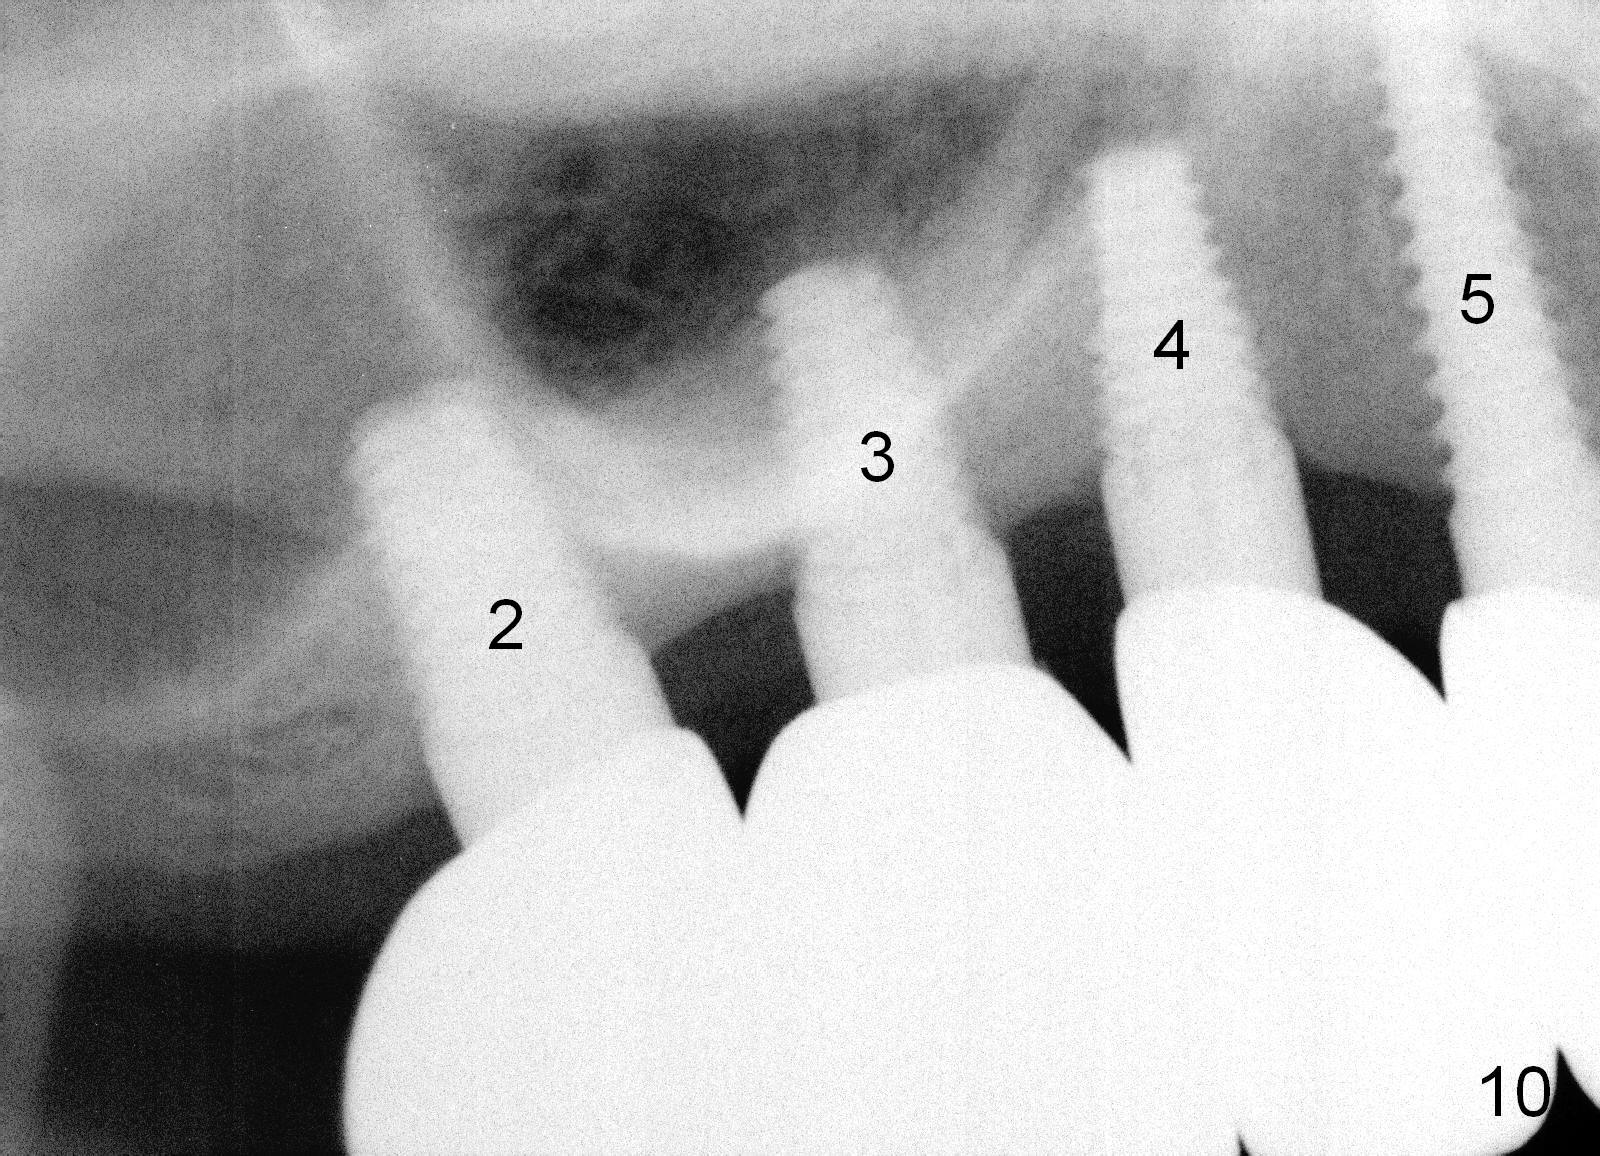

There is no apparent bone loss around the implants 13 months post immediate provisional, 5 months post cementation of non-splinted permanent restoration (Fig.10,11).